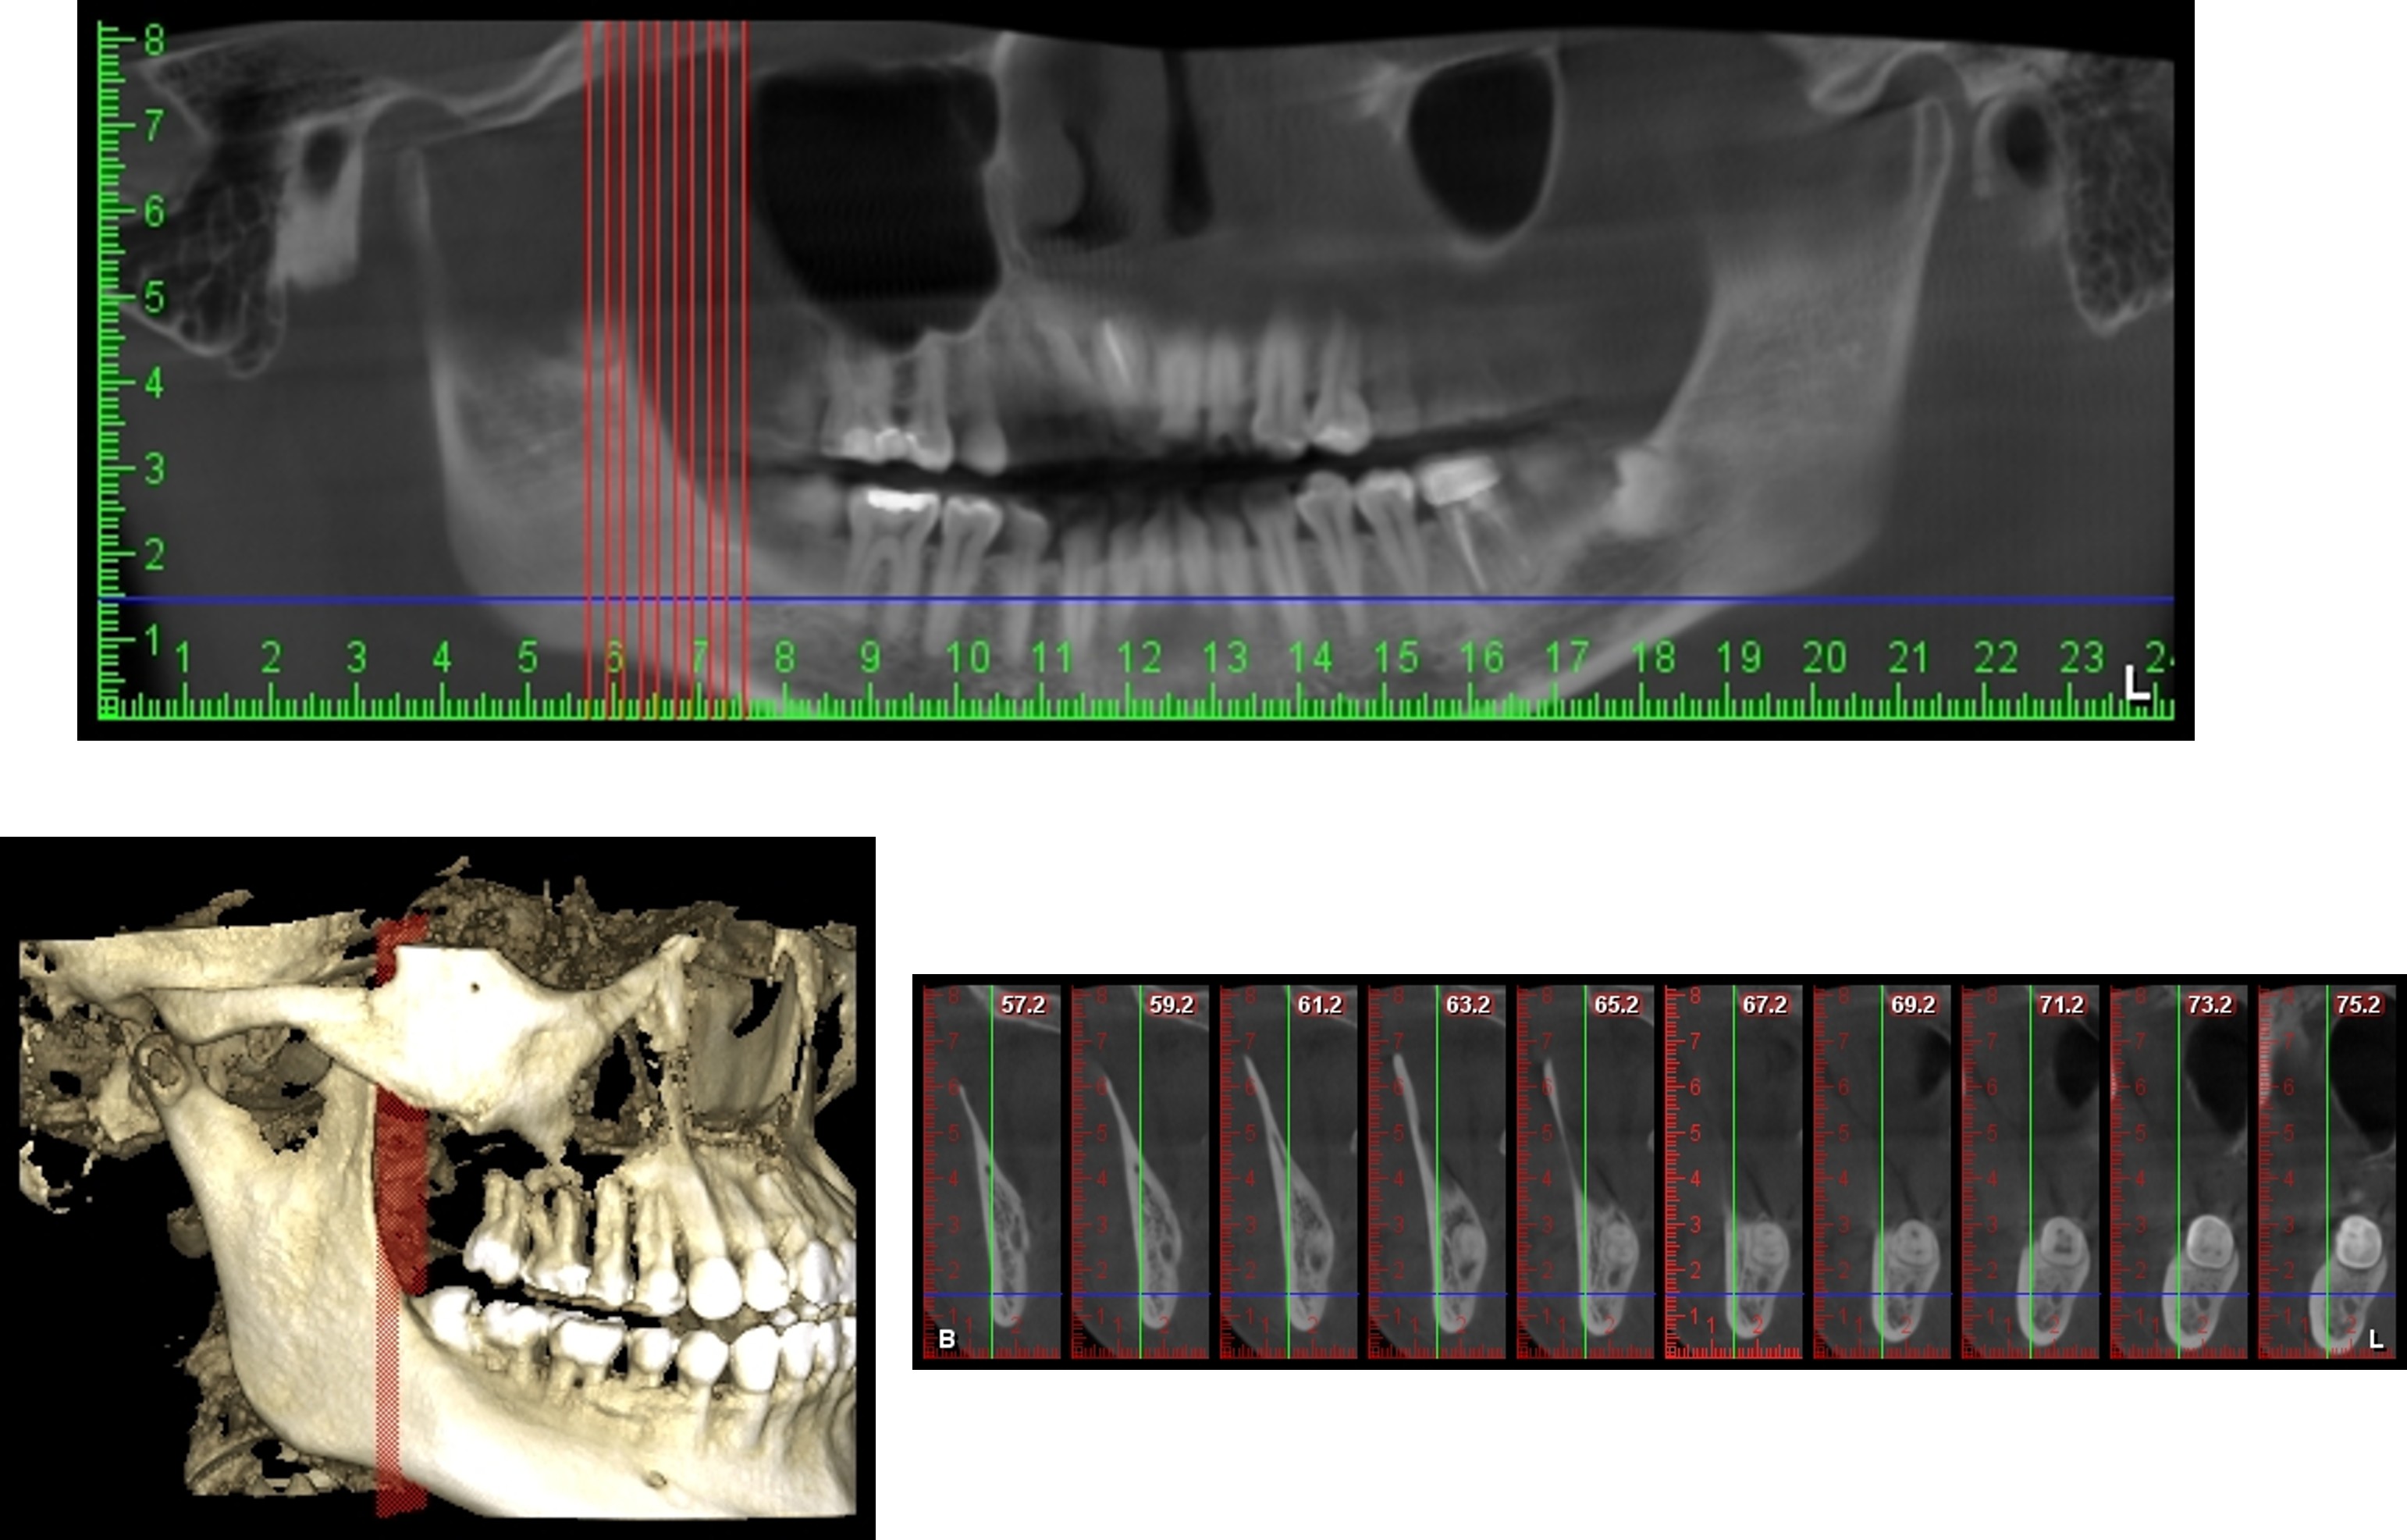

治療前,利用電腦斷層再次定位